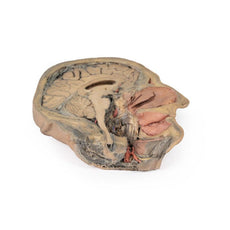

3D Printed Brain Hemisection

This 3D model is a midsagittal hemisection through a whole brain, preserving the right side anatomy and deep brain

structures and spaces visible in the midline. In lateral view, the right cerebral and cerebellar hemispheres are

covered in the arachnoid mater. In the midline view, the brain regions from the cerebrum to the medulla oblongata

are preserved. Centrally, the third ventricle is opened, with an intact septum pellucidum superiorly positioned and

obscuring the lateral ventricles within the cerebral hemisphere. On the inferior margin of the third ventricle both

the right mamillary body and right optic tract can be observed, whereas posteriorly the cerebral aqueduct can be

observed extending across the midbrain between the tectum and tegmentum towards the fourth ventricle (between the

cerebellum and pons). The cerebellum is separated from the occipital lobe by a preserved portion of the tentorium

cerebelli, and in cross-section the cerebellar cortex helps form the prominent arbor vitae.

A series of arterial

branches have been false coloured to contrast their course across the preserved brain structures. In the midsagittal

view the anterior cerebral artery courses from around the corpus callosum to supply the cingulate gyrus and other

midline cortical regions. The base of the middle cerebral artery can be seen passing deep between the temporal and

frontal lobes, with the posterior communicating artery connecting it to a small remnant of the posterior cerebral

artery. Adjacent to the posterior cerebral is the superior cerebellar artery, extending laterally to pass between

the temporal lobe and the cerebellum before passing deep into the transverse fissure.